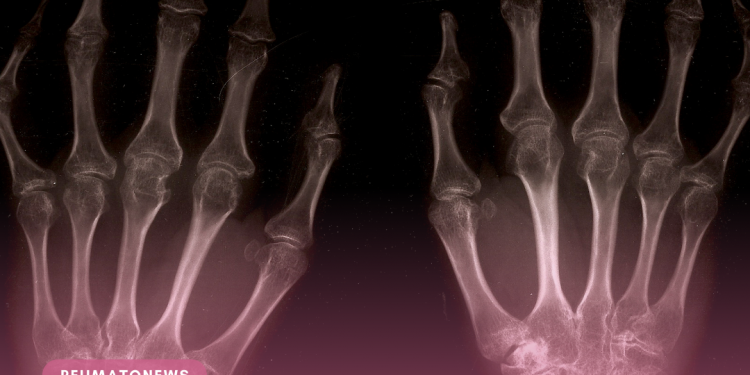

A inflamação das articulações é uma das caraterísticas principais da doença e pode provocar dor (que se agrava durante a noite), edema e, por vezes, vermelhidão e calor, além de poder causar também rigidez, uma sensação de prisão dos movimentos, principalmente no início da manhã ou depois de períodos de repouso. O normal é que a doença comece a manifestar-se com quatro articulações inchadas e dolorosas, nos dois lados do corpo, atacando inicialmente as pequenas articulações das mãos e dos pés. “À medida que a doença progride, mais articulações podem inflamar, incluindo ombros, cotovelos, ancas e joelhos”, explica o especialista.